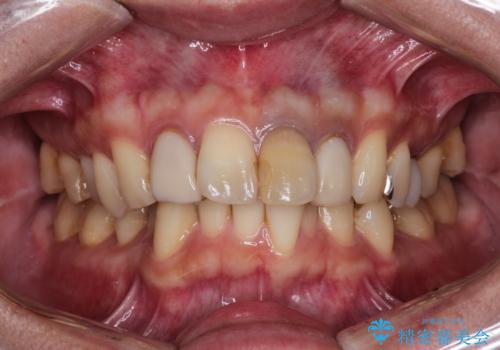

上の前歯の根元が黒い 根の治療を含めたセラミック再治療

- 上の前歯の根元が黒くなっているので、再治療をしたいとのことで来院された患者様です。

適合不良のかぶせ物をすべて除去して、根の中の治療から再治療を行うこととなりました。